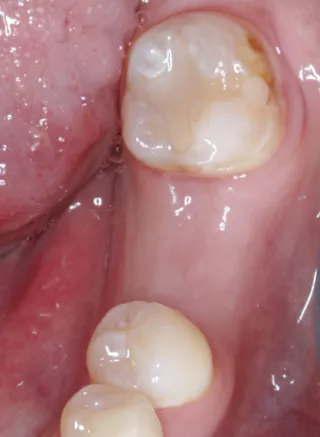

Unmittelbar im Anschluss an die OP erfolgte das Aufbringen eines Scan-Bodys (Straumann, CARES) mit digitaler Abformung der Implantatposition (Abb 14). Die Daten wurden unmittelbar über eine Cloud-Lösung auf den Arbeitsplatz des Zahntechnikers übertragen. Die Anfertigung der provisorischen Krone erfolgte durch Fräsen aus einem Kunststoffblock nach rein digitaler Planung (Abb. 15, 16; Labor Jörg Bies) in einem Zeitrahmen von zwei Stunden. Die provisorische Krone wurde direkt auf dem Implantat verschraubt (Abb. 17). Insbesondere wurde beim Einsetzen darauf geachtet, die periimplantäre Schleimhaut durch das Emergenzprofil der provisorischen Krone zu stützen. Die Okklusion wurde geprüft und die statische und dynamische Okklusion so weit reduziert, dass eine Interferenz durch Früh- und Störkontakte sicher ausgeschlossen werden konnte. Das postoperative Panoramaröntgenbild zeigt den korrekten Sitz von Implantat und Krone. Der Fadenzug erfolgte nach zehn Tagen bei sehr gut abgeheilten Wundverhältnissen.

Sechs Monate nach Implantation erfolgte die klinische und radiologische Kontrolle des Implantates. Bei solider Osseointegration und stabilen Schleimhautverhältnissen erfolgte daraufhin die Freigabe für die finale prothetische Versorgung des Implantates (Abb. 18).

Abb. 18: Röntgenkontrolle sechs Monate nach Insertion mit hervorragender Osseointegration unter Belastung.